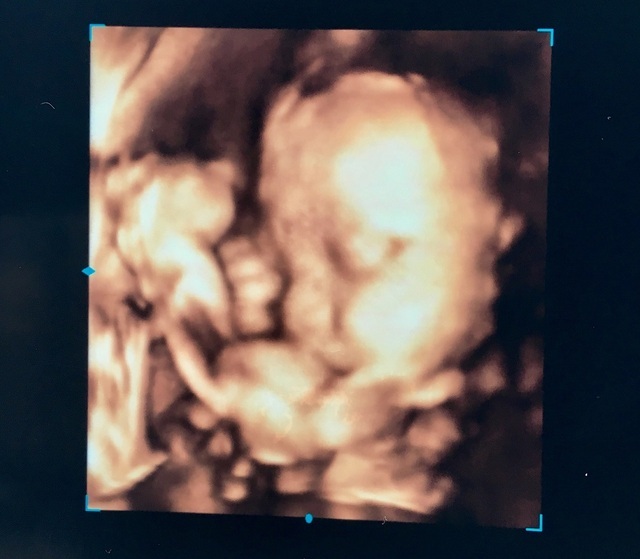

28週0日(28w0d)のエコー写真

28週0日(28w0d・女の子)|しおぽん さん(21歳)

エコー写真撮影時のエピソード:

初めて4Dエコーをみてとても感動しました。見た第一印象は鼻が低いなあって思いました(笑)でも、すごくかわいくてますます早く会いたくなりました。

あと、予定日まで1ヶ月きっていて正産期に入ってるので不安ですが頑張りたいです。